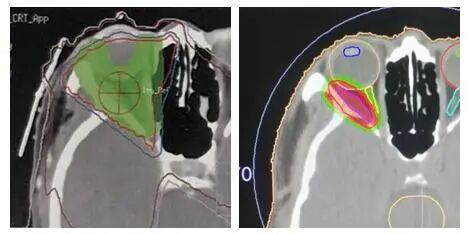

眼內也會得腫瘤?精準放療根治腫瘤同時讓視力無損